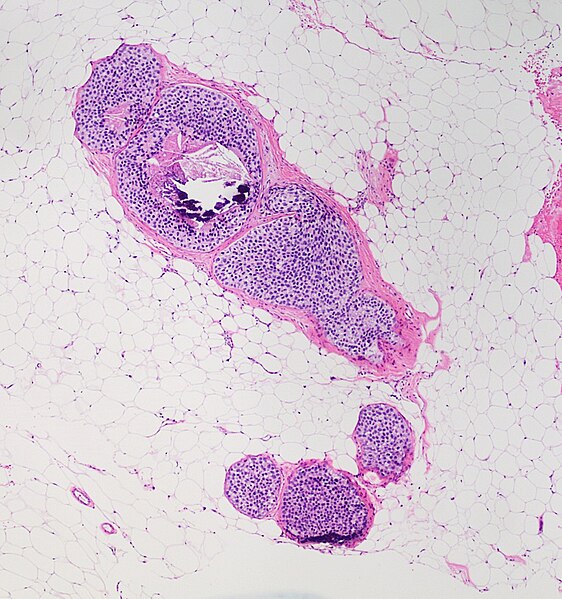

1. Use this image for the next two questions. A 42-year-old woman presents to the clinic with a left breast mass for 1 month. She does not have history of trauma. She has had type 2 diabetes for 5 years and has been treated with metformin. Her family history is significant for multiple cancers including endometrial carcinoma and benign ovarian tumors. Physical examination reveals a 2.5 cm mobile firm mass at the outer upper quadrant of her left breast. No other abnormalities are noted. An image of her biopsy is shown. What is the diagnosis?

A. Diabetic mastopathy

B. Fibroadenoma

C. Fibrocystic changes

D. Invasive ductal carcinoma

E. Invasive lobular carcinoma

F. Usual ductal hyperplasia

2. A 42-year-old woman presents to the clinic with a left breast mass for 1 month. She does not have history of trauma. She has had type 2 diabetes for 5 years and has been treated with metformin. Her family history is significant for multiple cancers including endometrial carcinoma and benign ovarian tumors. Physical examination reveals a 2.5 cm mobile firm mass at the outer upper quadrant of her left breast. No other abnormalities are noted. An image of her biopsy is shown. What is the diagnosis?

What will be the most likely immunohistochemistry study finding?